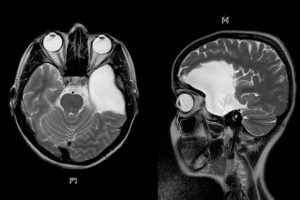

Araknoid Kist

Araknoid Kist Nedeni Belirtileri Tedavileri